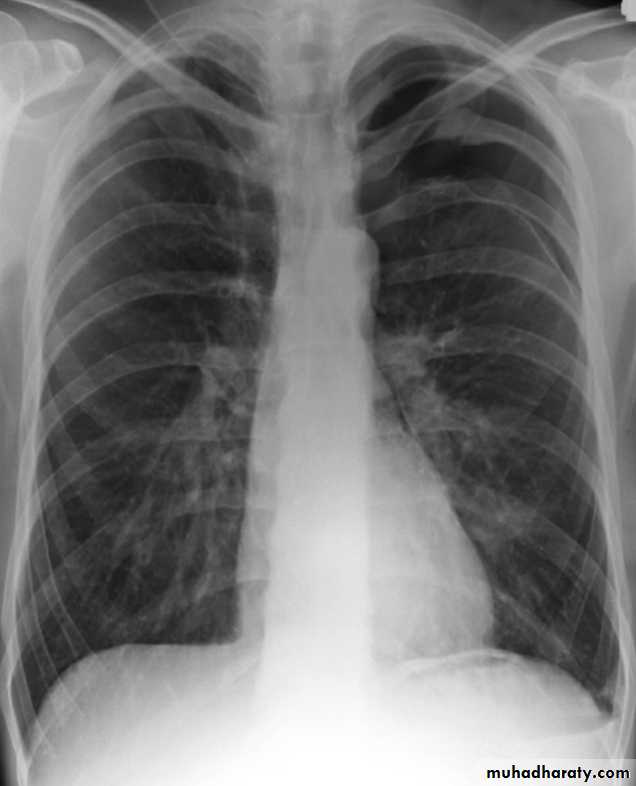

Radiolucent area devoid of lung markings in the upper left lung

Visible viseral pleural edge as very thin sharp white lineRadiolucent area devoid of lung markings in the upper left lung

Visible viseral pleural edge as very thin sharp white linePneumothorax

Radiolucent area devoid of lung markings in the periphry of the right lung with visible viseral pleural edge